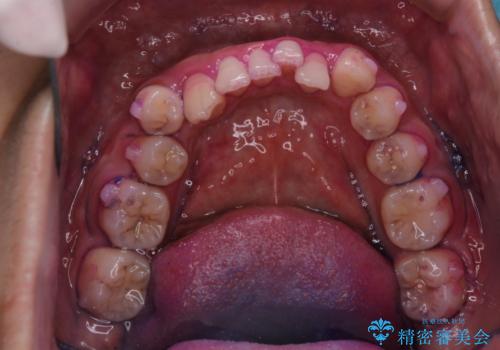

- マウスピース矯正中に、口臭が気になりクリーニングを行いたいとのことでした。染め出しをしての歯ブラシ指導とPMTC60分コースを行いました。

口腔内にはたくさんの細菌がいるため、ヌルヌルとしたプラーク(歯垢)が自然に歯の表面に付きます。

このプラーク(歯垢)にはたくさんの細菌が潜んでおり、虫歯や歯周病・口臭などの最大の原因です。そのため、毎日の歯磨きでプラーク(歯垢)をキレイに取り除くことが、健康な歯を保つためには欠かせません。

しかし、プラークは歯の色と似ているため、見ただけでは付着しているかどうかがハッキリとは分かりません。

染め出し液を使ってプラークを染め出すことにより、普段の歯みがきで磨き残している場所を目で確かめることができます。

日々の歯磨きを上達するには、まずどこが磨けていないか認識することが大切です。